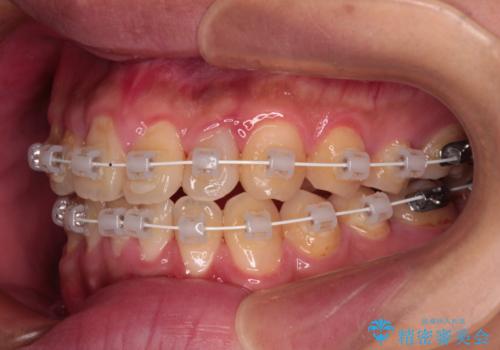

- 審美装置

一日中マウスピースを装着する煩わしさから、マウスピース矯正を継続する自信がないとのことで、ワイヤー装置にて矯正治療を行うこととしました。

気になっていたクロスバイトは速やかに改善され、1年間で治療を終えることができました。

治療開始前は汚れが多く、全体的に歯肉が腫れていましたが、矯正治療を通して腫れも少しずつ改善されました。